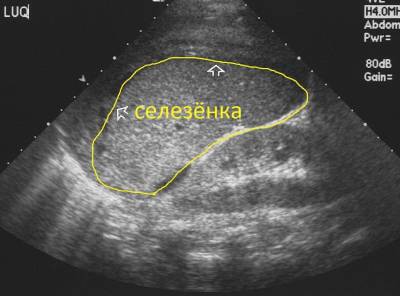

- Секвестрационный. При нём происходит угнетение клеточного ростка, увеличивается и болит селезёнка и печень.

- Увеличение селезёнки и печени.

- Увеличивается печень и селезёнка

На этом этапе гемолиз начинает снижаться, а селезёнка сморщивается от инфарктов органа.

УЗИ внутренних органов

Если при исследовании врач использует допплер, то можно понять были ли у пациента инфаркты органов, нормальный ли в них кровоток.